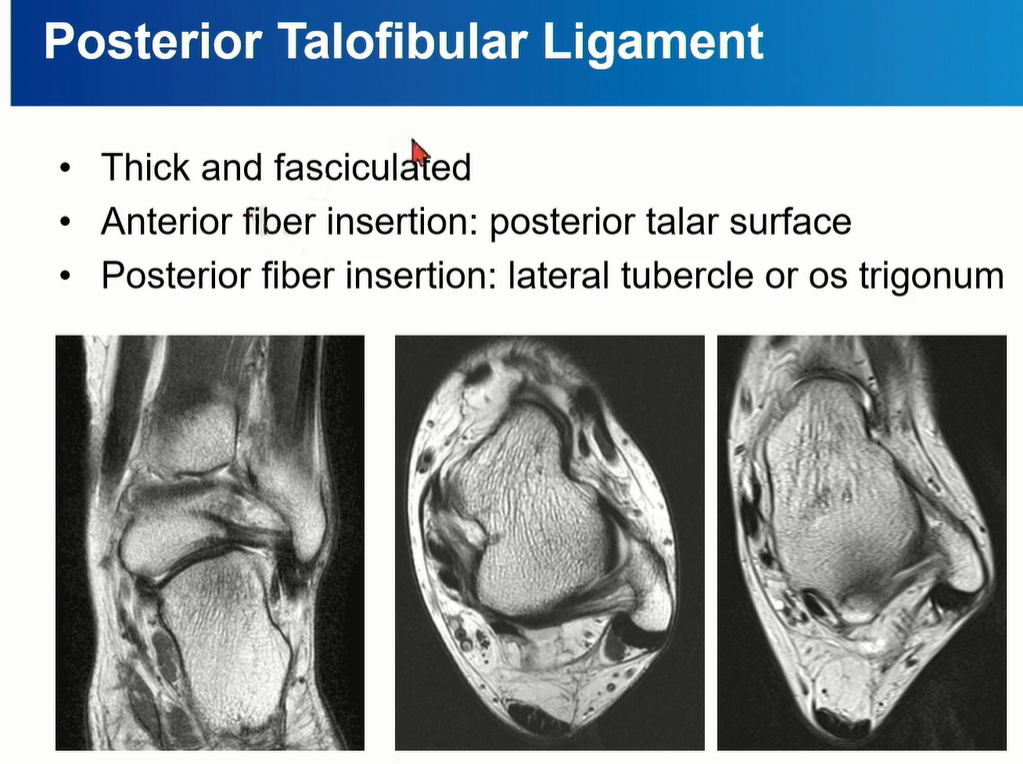

2-3 . PTFL (posterior talofibular ligament)

3가지 중에서 가장 두껍고 튼튼해서 injury가 제일 적다. 정상적인 상태에서도 ligament 내부로 fat portion이 있음.